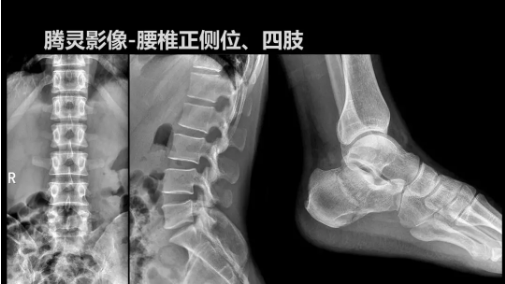

“騰靈”是安健科技的第四代動(dòng)態(tài)DR產(chǎn)品,可實(shí)現(xiàn)全科室應(yīng)用。如各類常規(guī)的X線檢查、消化道檢查、骨科檢查、婦科、兒科檢查等。此外,安健科技為“騰靈”在真正意義上實(shí)現(xiàn)多科室、多功能診斷進(jìn)行了多項(xiàng)針對(duì)性設(shè)計(jì)。

其中包括SID范圍可調(diào)節(jié)能夠滿足多種類攝影要求、球管角度可調(diào)節(jié)能夠滿足不同投照部位的需求、超低床體設(shè)計(jì)方便患者上、下床、360°可旋轉(zhuǎn)腳踏板降低擺位難度、可移除式濾線柵能夠滿足兒科等特定場景的計(jì)量要求、可升降操控臺(tái)方便醫(yī)生床旁操作等,并配置了全身拼接功能,最大程度上適配動(dòng)態(tài)DR產(chǎn)品的特點(diǎn)。

相較前代產(chǎn)品,“騰靈”在圖像質(zhì)量方面得到了全面升級(jí),“騰靈”采用17*17非晶硅平板探測器設(shè)計(jì),采集矩陣達(dá)3072*3072,動(dòng)態(tài)范圍達(dá)16bit,為成像提供超大視野的同時(shí)保證成像質(zhì)量,此外,該款機(jī)型可根據(jù)醫(yī)療機(jī)構(gòu)的差異化需求而選配不同的動(dòng)態(tài)平板探測器,以此來適應(yīng)不同階層用戶所需。